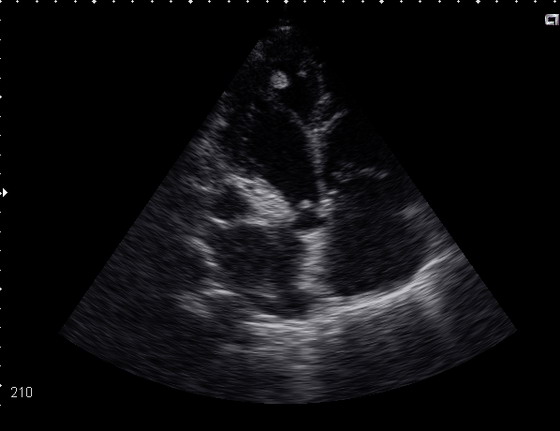

Мужчина, 40 лет, поступил в кадиологическое отделение с жалобами на сердцебиение, слабость. При обследовании: ЭКГ мерцательная аритмия. тахисистоличская форма с ЧСС 175 в мин. признаки ишемии передне-боковой стенки, перегрузка правого желудочка. ОАК. ОАМ без особенностей.

ЭхоКГ: ПЖ-40см, ЛЖ КДР -65,КДО-178мл, КСО-121мл, МЖП сис.11см\ диаст.12, ЗСЛЖ сис 11\13, ФВ- 32%, давление в легочной артерии 14ммHg, умеренная дилтация ЛП и ПП ( регургитация митральная 1 ст. трикуспидальная 2ст).

В области верхушки левого желудочка лоцируются 2 округлых образования одно из котрых находится на дополнительной хорде. Есть мнение, что это внеклапанный бак.эндокардит, а есть, что это миокардит с тромбом верхушки ЛЖ. Ваше мнение?

Внешне структуры в области верхушки мало похожи на тромб. Можно попробовать рассмотреть эту зону с помощью конвекса с бОльшей частотой сканирования. В целом, клиническая оценка состояния пациента может быть более полезной для диагноза, чем гадания по УЗ-картинке.

Сегодня у больного развилась клиника инфаркта мозга. При ЭхоКГ в области верхушки никаких дополнительных структур не обнаружено.

Учитывая клинику, лабораторные данные (не было ни лейкоцитоза, ни высокого СОЭ, а бакэндокардит-это всё же септическое состояние, и кстати, в последнем анализе СОЭ было 0.5мм\ч) думаю вероятнее это был тромб. :?:

Описанная ЭХО-картина в большей степени соответствует ДКМП, чем инфекционному эндокардиту. А для ДКМП (или если хотите миокардита Абрамова - Фидлера) характерно пристеночное тромбообразование. А тем более на фоне фибрилляции предсердий